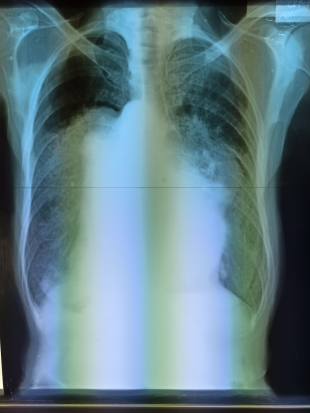

We receive support at the clinic from local visiting physicians. Dr. T. is a general practitioner, Dr. M. a pediatrician. However, I still see most of the patients myself, as they prefer the "American Doctor." Patients come from all over the province and travel long distances. Unfortunately, we often see patients with advanced illnesses, which is undoubtedly due to the pandemic, as residents were only able to leave their villages with great difficulty and rarely sought medical treatment. Many patients come with advanced tuberculosis, high blood pressure, and, unfortunately, also diabetes, which is due to a lack of exercise (due to the heat) and high rice consumption. In addition, many patients come for wound care, as doctors in the city often don't even bother to open the bandages and examine the wounds. Instead of complex and lengthy wound care, they prefer amputation, which is very drastic in a country like the Philippines, as the necessary aids to make daily life easier for people with leg amputations, for example, are lacking. Over the years, state-provided healthcare has improved, with more doctors and specialists. Still, trust is lacking, and patients particularly appreciate the personal attention they don't get at local hospitals or from general practitioners. In addition to the clinic, I also make home visits, especially when patients don't want to go to the hospital, are immobile, or are dying.